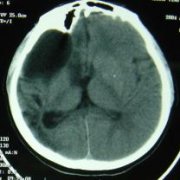

半球脑软化继发癫痫案例

患者张某,女性,11岁(入院时年龄) 患者出生70天时无明显诱因下出现一次肢体抽搐,身体倾倒,头偏一侧,伴意识丧失,持续约2-3分钟后自行缓解。3天后出现双眼上视,愣神,持续约1分钟,缓解,未于抗癫痫治...【详细】